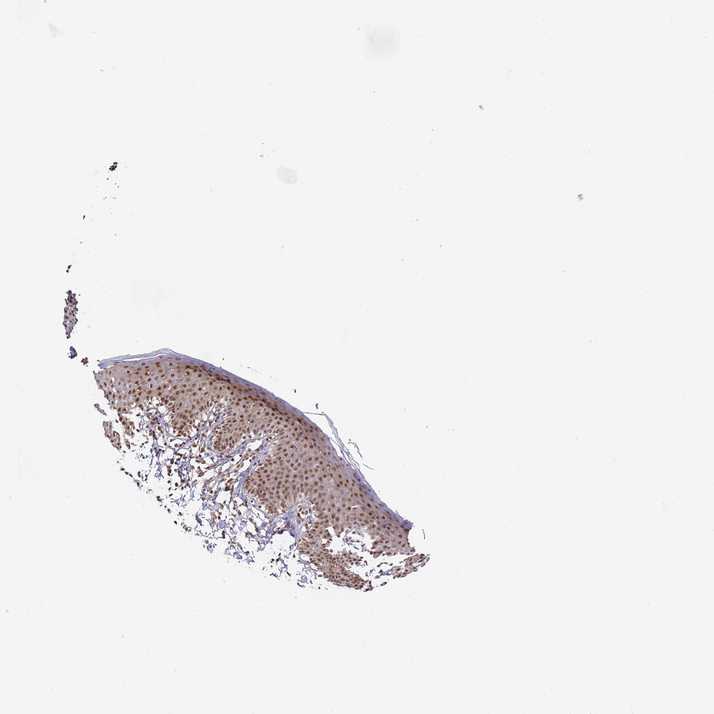

SKIN 1 - Antibody stainingi

Antibody staining in the annotated cell types in the current human tissue is reported as not detected, low, medium, or high, based on conventional immunohistochemistry profiling in selected tissues. This score is based on the combination of the staining intensity and fraction of stained cells.

Each image is clickable and will lead to virtual microscopy that enables deeper exploration of all samples and also displays staining intensity scores, fraction scores and subcellular localization as well as patient and tissue information for each sample.

Antibody HPA043258Antibody HPA043621

Langerhans MediumMedium

Fibroblasts MediumMedium

Keratinocytes MediumMedium

Melanocytes MediumMedium